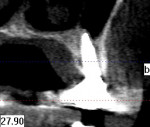

The area was irrigated with 0.12% chlorhexidine gluconate, and a cone-beam computed tomography (CBCT) was exposed to determine if implant placement using an allograft ring was an option. The scan revealed that an implant could be placed in a restoratively driven fashion utilizing the apical native bone, which would stabilize the fixture and allograft ring (Figure 4). Sinus involvement was ill-advised due to the patient's smoking addiction. It was decided to use a Narrow Connection Straumann® Bone Level Tapered Implant in position No. 12 and a Regular Connection Straumann® Bone Level Tapered Implant in position No. 13, necessitating the use of a 7-mm diameter Straumann® AlloGraft Ring. Standard surgical protocol was followed in the preparation of the osteotomy for the allograft ring and implant. This included identifying the appropriate site, marking it with round burs, and drilling to depth with a 2.2-mm diameter twist drill. A 7-mm trephine with copious irrigation was used to create the osteotomy, and a planator was used to flatten the floor.

Healing was uneventful. A full 6 months was allowed for hard- and soft-tissue maturation (Figure 10). An implant stability quotient (ISQ) value (Osstell, osstell.com) of 68 for the grafted site was noted at stage II, which is very good for type IV bone (Figure 11). The final restorations were fabricated, consisting of four individual units for teeth Nos. 11 through 14 (Figure 12). The periapical x-ray taken shortly after delivery of the prosthetics depicted osseointegrated implants in position Nos. 12 and 13 (Figure 13). The CBCT revealed that the implant in position No. 13 was well positioned and demonstrated complete regeneration of the buccal plate (Figure 14).